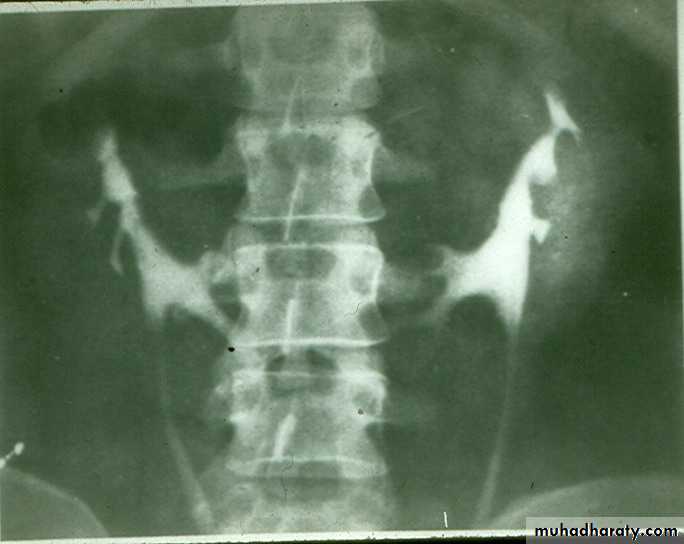

Radiological appearance :-

IVU findings

1- Large size kidney .

2- Local indentation of out-line .

3- Unilateral or bilateral .

Ultrasound findings:

Division of renal sinus

CONGENITAL ANOMALIES OF THE URINARY TRACT

duplication